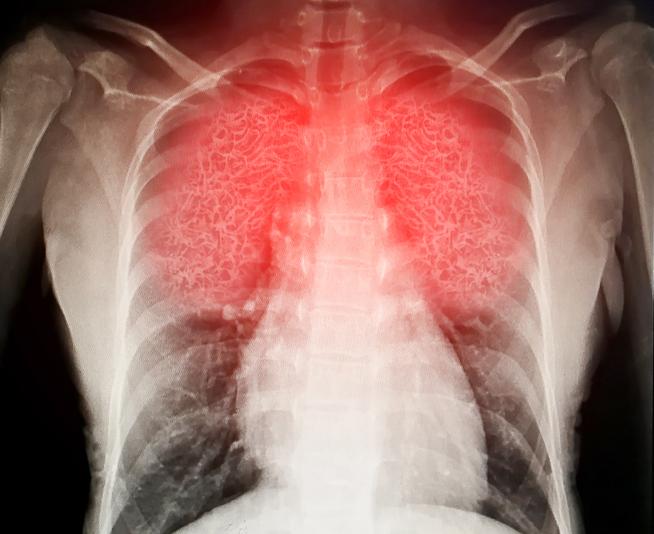

Poitrine et poumons

Problèmes thoraciques et pulmonaires

Qu'il s'agisse d'affections de longue durée ou d'infections soudaines, les problèmes thoraciques et pulmonaires peuvent toucher n'importe qui. Apprenez-en les causes et comment les gérer efficacement.